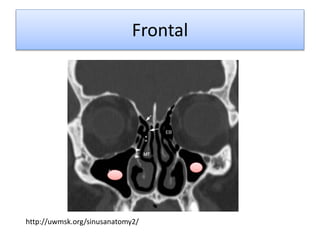

Frontal

http://uwmsk.org/sinusanatomy2/